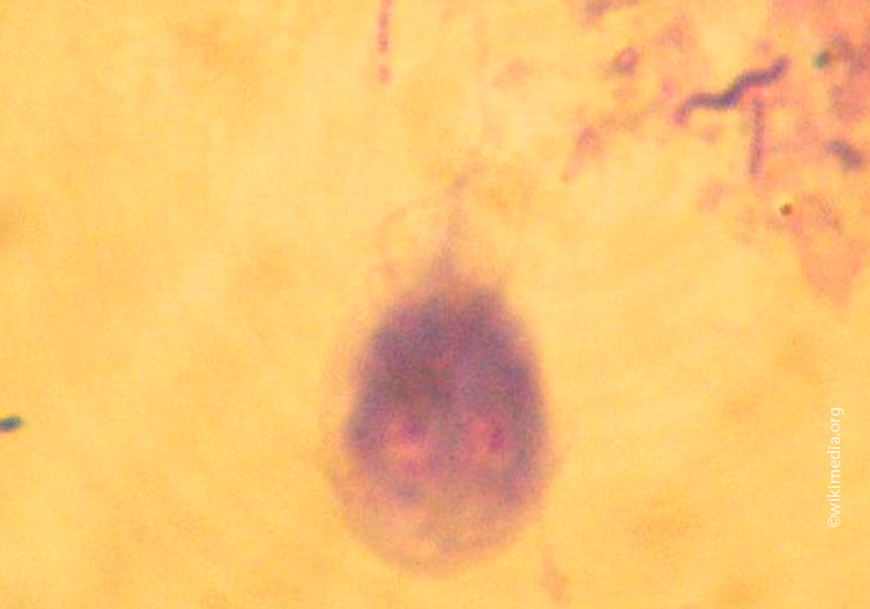

Диагноз при гиардиозе у собак и кошек ставят на основании обнаружения подвижных трофозоитов в свежих фекалиях или смывах из двенадцатиперстной кишки, а также при обнаружении цист с помощью флотационного метода, или протеинов лямблий с помощью ELISA. Раствор сульфата цинка является наиболее подходящей средой для визуализации цист (особенно после центрифугирования), так как другие растворы могут их деформировать. Как минимум три анализа кала должно быть проведено в течение 7-10 дней прежде, чем исключить лямблиоз.

Некоторые ELISA техники анализа кала (например, SNAP, Giardia Test, Idexx Laboratories) имеют высокую чувствительность и проще в применении, чем флотационный метод. Смывы из просвета двенадцатиперстной кишки (получаемые эндоскопически или хирургически путем введения в просвет и последующего забора 5-10 мл физиологического раствора) или цитологическое исследование слизистой двенадцатиперстной кишки иногда позволяют выявить Giardia, когда другие техники не способны. Трофозоиты Giardia.